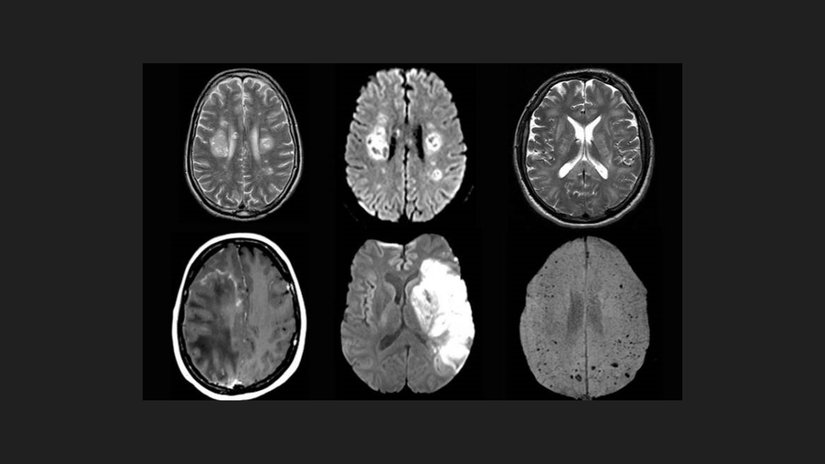

2022 yılında University of Oxford öncülüğünde yapılan ve UK Biobank adlı geniş çaplı veri tabanından faydalanılan bir çalışmada, araştırmacılar 785 bireyin beyin MRI görüntülerini analiz etti. Bu kişilerden 401’i COVID-19 geçirmiş, geri kalan 384’ü ise kontrol grubunu oluşturuyordu. Önemli olan nokta: COVID öncesi ve sonrası MRI görüntüleri karşılaştırılarak değişimlerin yönü incelendi.

Çalışma sonuçlarına göre, enfeksiyon geçiren kişilerin özellikle orbitofrontal korteks ve parahipokampal girus gibi alanlarında gri madde kaybı tespit edildi. Aynı zamanda, genel beyin hacminde küçülme ve bilişsel işlevlerde (örneğin dikkat, tepki süresi) düşüşler gözlendi. İlginç şekilde, bu değişimler hafif semptomlarla hastalığı geçiren kişilerde bile gözlemlendi. Benzer şekilde, 2023’te yayımlanan başka bir çalışmada da COVID-19 sonrası beyin omurilik sıvısında nörodejenerasyona işaret eden biyobelirteçlerde artış saptandı. Bu da bazı araştırmacıları Alzheimer gibi hastalıklarla olası bağlantılar konusunda alarma geçirdi.

COVID‑19 geçiren bireylerde, kontrol grubuna göre hem gri madde kalınlığında, hem de tüm beyin hacminde daha fazla azalma saptandı. Özellikle koku ve hafıza ile ilişkili beyin bölgeler orbitofrontal korteks ve parahipokampal girus en çok etkilenen alanlardı.

Ortalama olarak, enfeksiyon grubunda MR’lar arasında %0.2 ila %2 arasında ek gri madde kaybı ya da doku hasarı gözlemlendi. Ayrıca, beyin ve omurilik sıvısı hacminde artış görüldü; bu da beyin dokusunda küçülmeye işaret eden bir bulgu. Yapısal değişimlerin yanı sıra, aynı bireylerde yapılan kognitif testler (dikkat, işlem hızı, hafıza vs.) de enfeksiyon sonrası düşük performansa işaret etti.